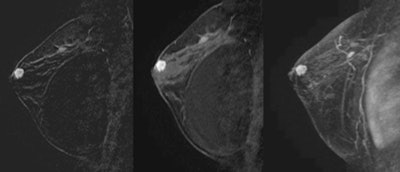

MRI shows an invasive ductal carcinoma abutting an implant in a 58-year-old woman with a palpable mass and retroglandular saline implants for 30 years. There is a spiculated mass abutting the superolateral implant. An outside mammogram and ultrasound failed to show the carcinoma.Breast MRI also found 13 cancers (24%) abutting the pectoralis muscle, with eight paralleling the muscle contour. Two cancers (4%) invaded the pectoral muscle.